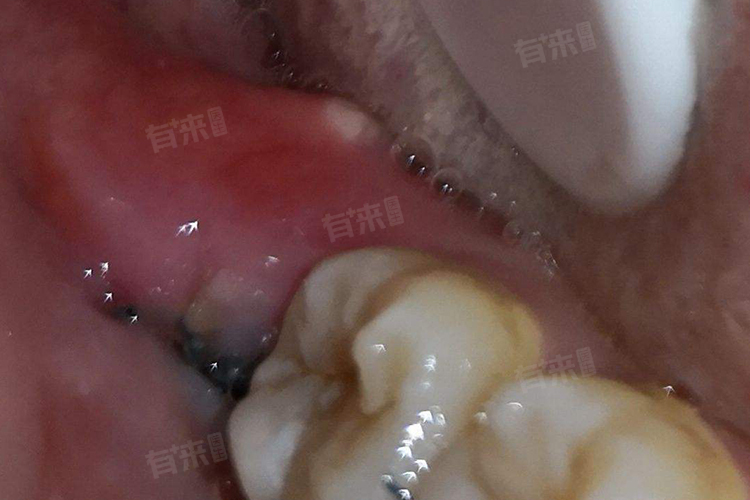

拔完智齿15天还不能张大嘴,这种情况可能由多种因素导致,如手术伤口未完全愈合、肌肉紧张或肿胀、感染等,需要根据具体情况采取相应的处理措施。建议及时就医检查,并在医生的指导下进行治疗和康复锻炼。

1、手术伤口未完全愈合:拔智齿是一项手术性操作,术后会留下伤口。如果伤口没有完全愈合,可能会导致嘴巴张不开。

3、感染:如果在恢复期间不注重局部的护理措施,可能会导致继发性细菌感染,引起局部组织的肿胀或伤口愈合不良,从而限制张口活动。如果存在感染,医生可能会开具抗生素类药物进行抗感染治疗。如果疼痛严重,可以咨询医生给出合适的止痛药物。